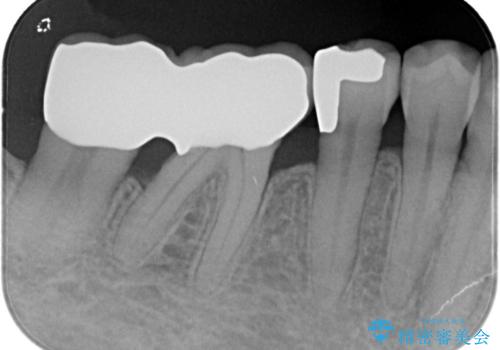

【PGAインレー】深い位置の二次カリエス

- 定期検診にて虫歯を発見したため、PGAインレーにて治療を行いました。

PGAインレーは金と白金を多く含み、精度高い修復が可能です。